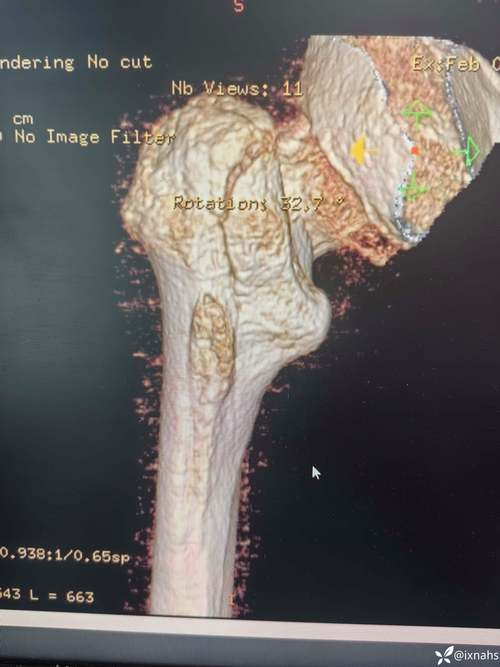

- 病例分析:如“患者,男,65岁,摔伤致右髋部疼痛、活动受限,X线示右股骨颈骨折,分型为Garden III型,请制定治疗方案并说明理由”,需涵盖分型依据(如Garden分型基于骨折移位程度)、手术方式选择(关节置换 vs. 内固定)、术后康复计划等。